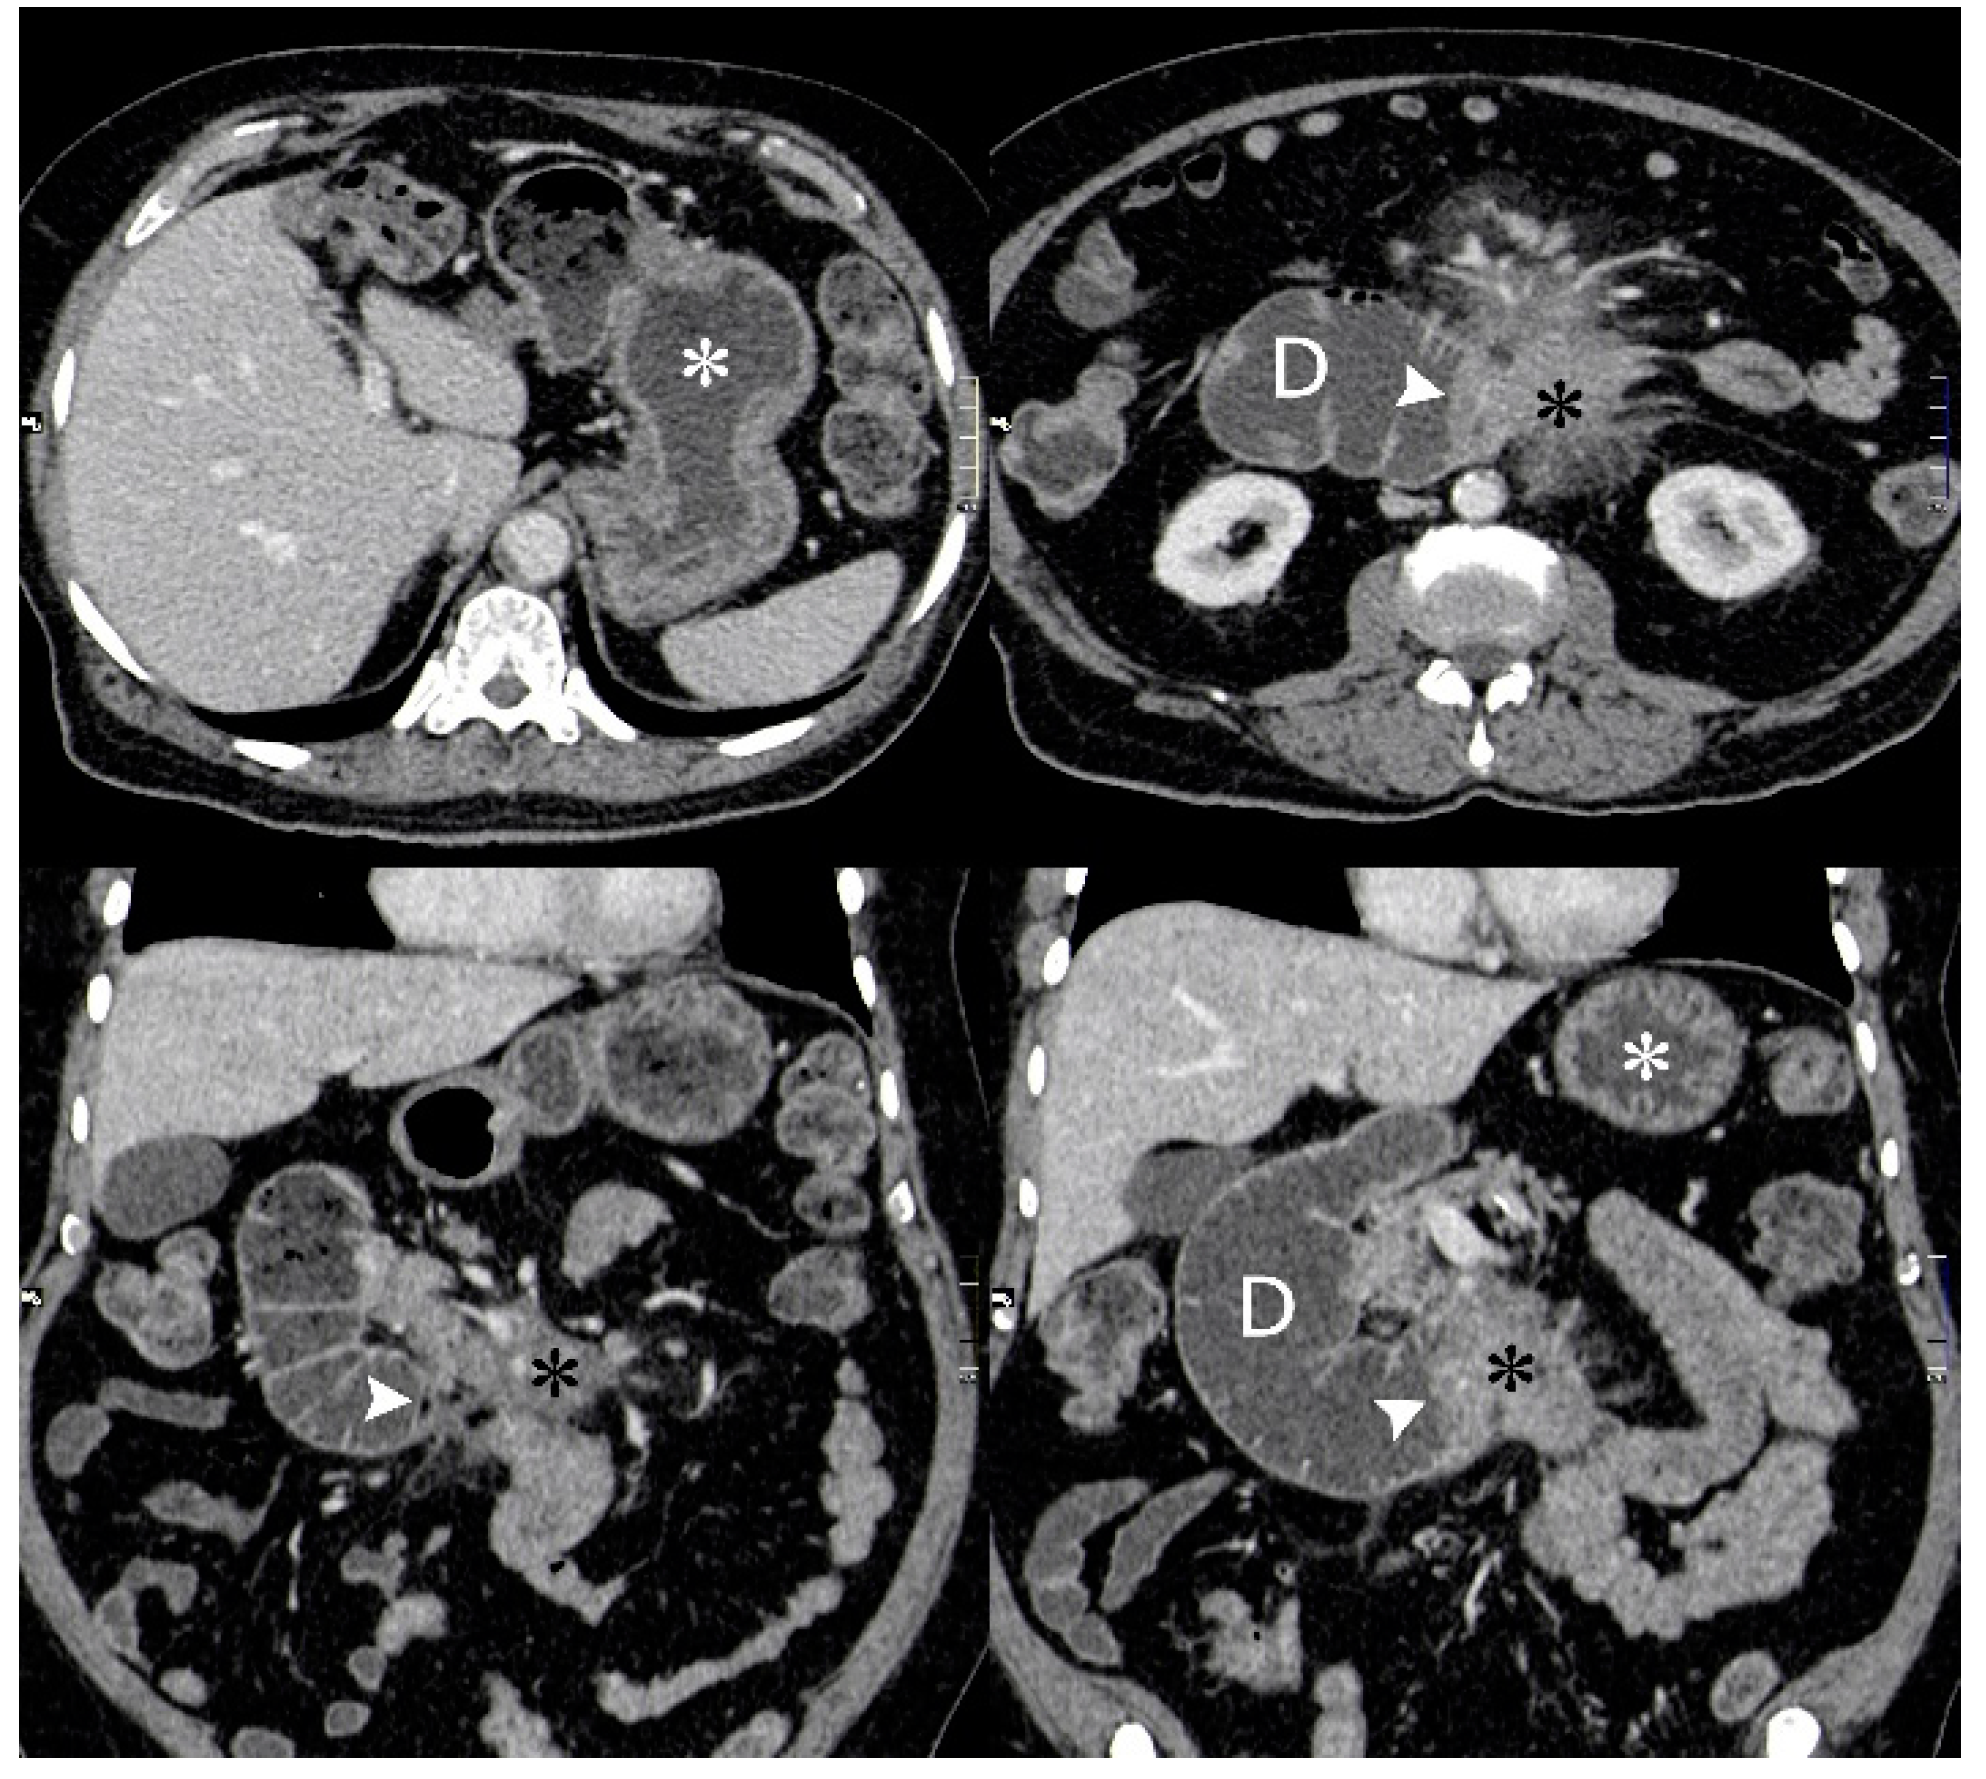

Computed Tomography (CT) of his chest, abdomen and pelvis showed a large (8 cm × 10 cm × 9.5 cm) mesenteric mass encasing the mesenteric vessels with proximal small bowel obstruction (Figure 2). There were multiple enlarged mesenteric and retroperitoneal lymph nodes.

Figure 2.

Axial (top row) and coronal (bottom row) CT images from an initial diagnostic portal venous phase contrast enhanced CT when patient presented with symptoms of gastric outlet obstruction. Fluid filled dilated stomach (white asterisk) and 2nd and 3rd part of duodenum. Ill-defined enhancing mass in the root of the mesentery (black asterisk) obstructing the 3rd part of the duodenum (white arrowhead).